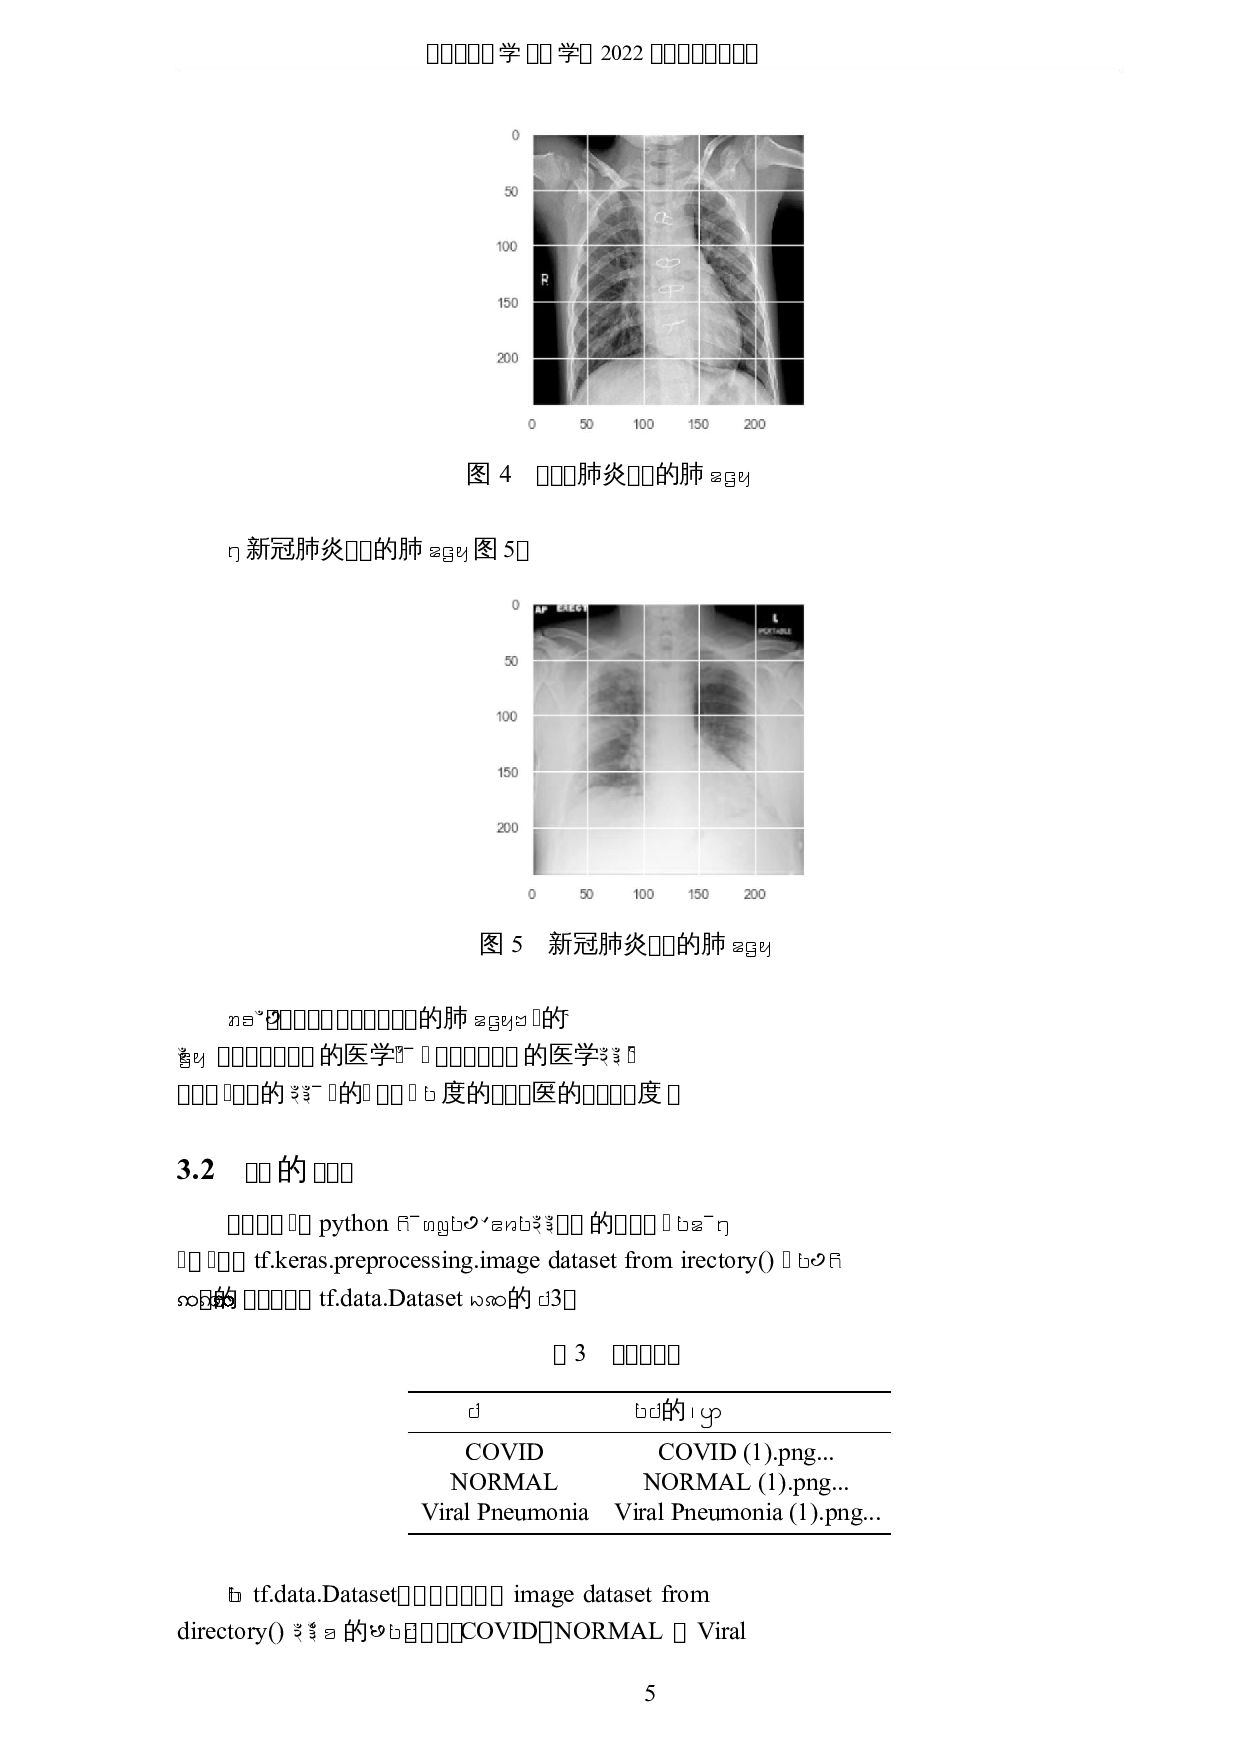

ꢠꢡꢃꢇꢍ学ꢢꢣ学ꢀ 2022 ꢤꢥꢌꢦꢧꢊꢨꢩ 基于深度学习的新冠肺炎医学图像研究 ꢇ ꢈ ꣞꣟꣓꣠深度学习ꢄ医꣡꣢꣣꣤꣥꣦的图像꣧꣨ꢎꢏꢳ꣩꣪꣫꣬꣭꣮꣛꣯的的 医꣡꣰꣱ꢳꢥꢩꣲꣳꣴ新冠肺炎的图像ꢂꢋꣵꣶꢂꢋꣷ꣸ꢃ꣹꣺图像ꣻ꣼ꢳꣽꣾ꣞ ꣇ꣿ的꤀꤁꤂ꢵ꤃ꣻ꤄꤅基꤆的꤇的꣖ꢱ꤈꤉꤃ꣻꢼꢳꤊꤋ꣑ꢾ tensorflow ꣵꣶꤌ ꤍꤎꤏꤐꤑ꤀꤁ꤒ CNN ꤓ的ꤔ꤂꣹꣺图像꣸ꢃꢳꤕ꣇ꤖ꣑ꢾ꣸ꢃ꣇的图像ꢂꢋꣵꣶ ꣻꤗꤘꤙ꣖ꤚ꣇꣑ꢾꤛꤜꤝꣲ꤀꤁ꣵꣶꤛꤜꢳꤞꤟꣻꤗ的꤀꤁ꤠꤡꤢ꣞ 95.23% ꣖ꢱ ꤈ꤣ꤃ꣻꢳꢥꢩ꣑ꢾ꣟基于 CT 图像ꢄꤞꤟ图像的꣤ꤤꤥꣂꢳ꣑ꢾ꣟ pytorch ꣹꣺ꤦ ꢾ꣟ torchXrayVision ꢼꣷꤘꤙ꤅的꤀꤁ꣵꣶꤧꤨ学习的图像ꤘꤙꢳꤚꤩ꤀꤁的ꤪꤡ ꤢ꣞ 75% ꣖ ꢀꢁꢂꢃ 新冠肺炎꤫ CNN ꤫图像ꣻꤗ꤫ torchXrayVision ꤫ꤧꤨ学习 ꢠꢡꢃꢇꢍ